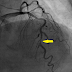

Fig. 2は、冠動脈造影像です。PCIになるものとばかり考えていましたのでNTG投与下の造影です。#6には50%狭窄しかありません。

| Fig. 2 Left Coronary Artery after NTG IC |

しかし、今回のような例を見ると冠動脈CT前にNTGの使用は避けて通れないものと思えます。明日以後の冠動脈CT撮影時にはNTG舌下を先行させるプロトコールに変更することにしました。心拍数のコントロールには最近、冠動脈CT用に使用が認められたコアベータを使用するつもりです。この方法で検査をすればいつ効いてくるかわからない内服のベータブロッカーの効果発現を待たなくても済みます。